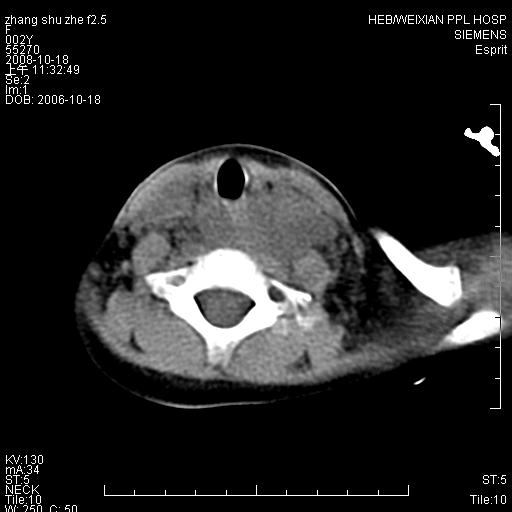

以下是引用dyqct在2009-2-10 21:04:00的发言:[br]年龄?性别?有发烧吗?[br]鼻咽部、口咽部、喉咽部及颈椎前间隙广泛肿厚,明显占位效应并致相应组织变形。ct值22-28hu。[br]考虑:1、颈前脓肿可能性大;[br] 2、建议增强或治疗后复查。

以下是引用jiangjing在2009-2-11 11:37:00的发言:[br]急性病程,鼻咽部、口咽部、喉咽部及颈椎前间隙广泛肿厚,明显占位效应并致相应组织变形.考虑颈部感染性病变(脓肿?);建议行进一步检查。